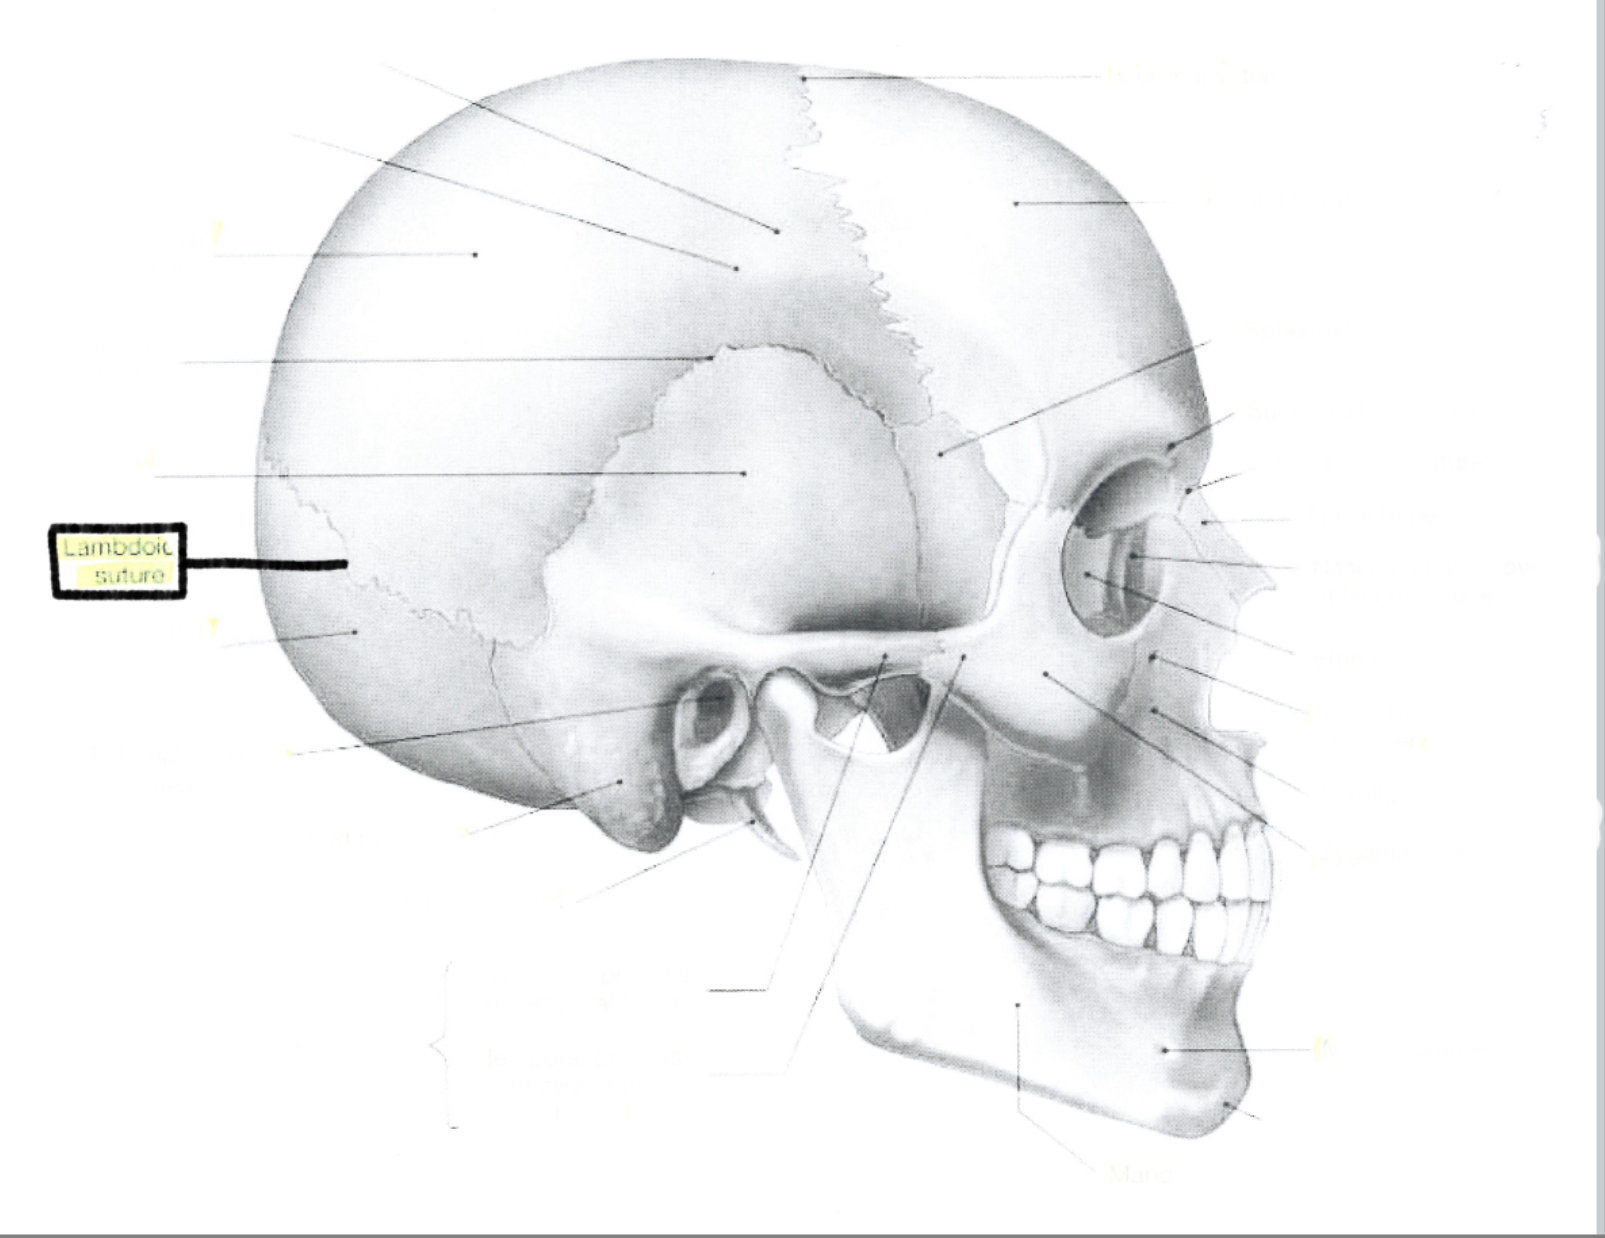

What is this?

Lamboid suture